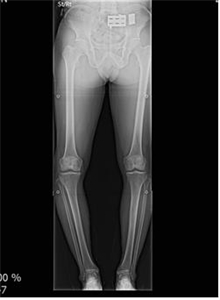

°­µ¿°æÈñ´ëº´¿ø, ÀÚ¿¬Ä¡¾Æ¿Í °¡Àå À¯»çÇÑ ÀÓÇöõÆ® ¡®3D ½Ã¼ú¡¯ °­Á¡

ÄÄÇ»ÅÍ À̹ÌÁö ¸ðÀǽüú ÈÄ È¯ÀÚ¸ÂÃãÇü ¼ö¼ú ½ÃÇà /ÃÖ¼Ò Àý°³ ½Ã¼ú·Î º×±â¡¤ÅëÁõ °ÅÀÇ ¾ø°í ȸº¹µµ »¡¶ó Çѱ¹Àº Àü Àα¸ÀÇ 14%°¡ 65¼¼ ÀÌ»ó °í·ÉÃþÀ¸·Î ÀÌ...

[°­µ¿±¸ ´Þ·Á¶óº´¿ø ÀåÁ¾ÈÆ ¿øÀåÀÇ ÀÇÇлó½Ä] ¹«¸­ °üÀý¿°À¸·Î À̾îÁö´Â ÈØ´Ù¸®, Ä¡·á Çʼö

¹«¸­ °üÀý¿°À¸·Î À̾îÁö´Â ÈØ´Ù¸®, Ä¡·á Çʼö "ȯÀںР³ªÀ̰¡ 45¼¼µµ ¾ÈµÇ¾ú´Âµ¥, ¹«¸­Àº 70´ë ¹«¸­À̱º¿ä. ÀÌ ³ªÀÌ¿¡ Àΰø°üÀý ¼ö¼úÀ» ÇÒ ¼öµµ ¾ø°í Å«ÀÏ...